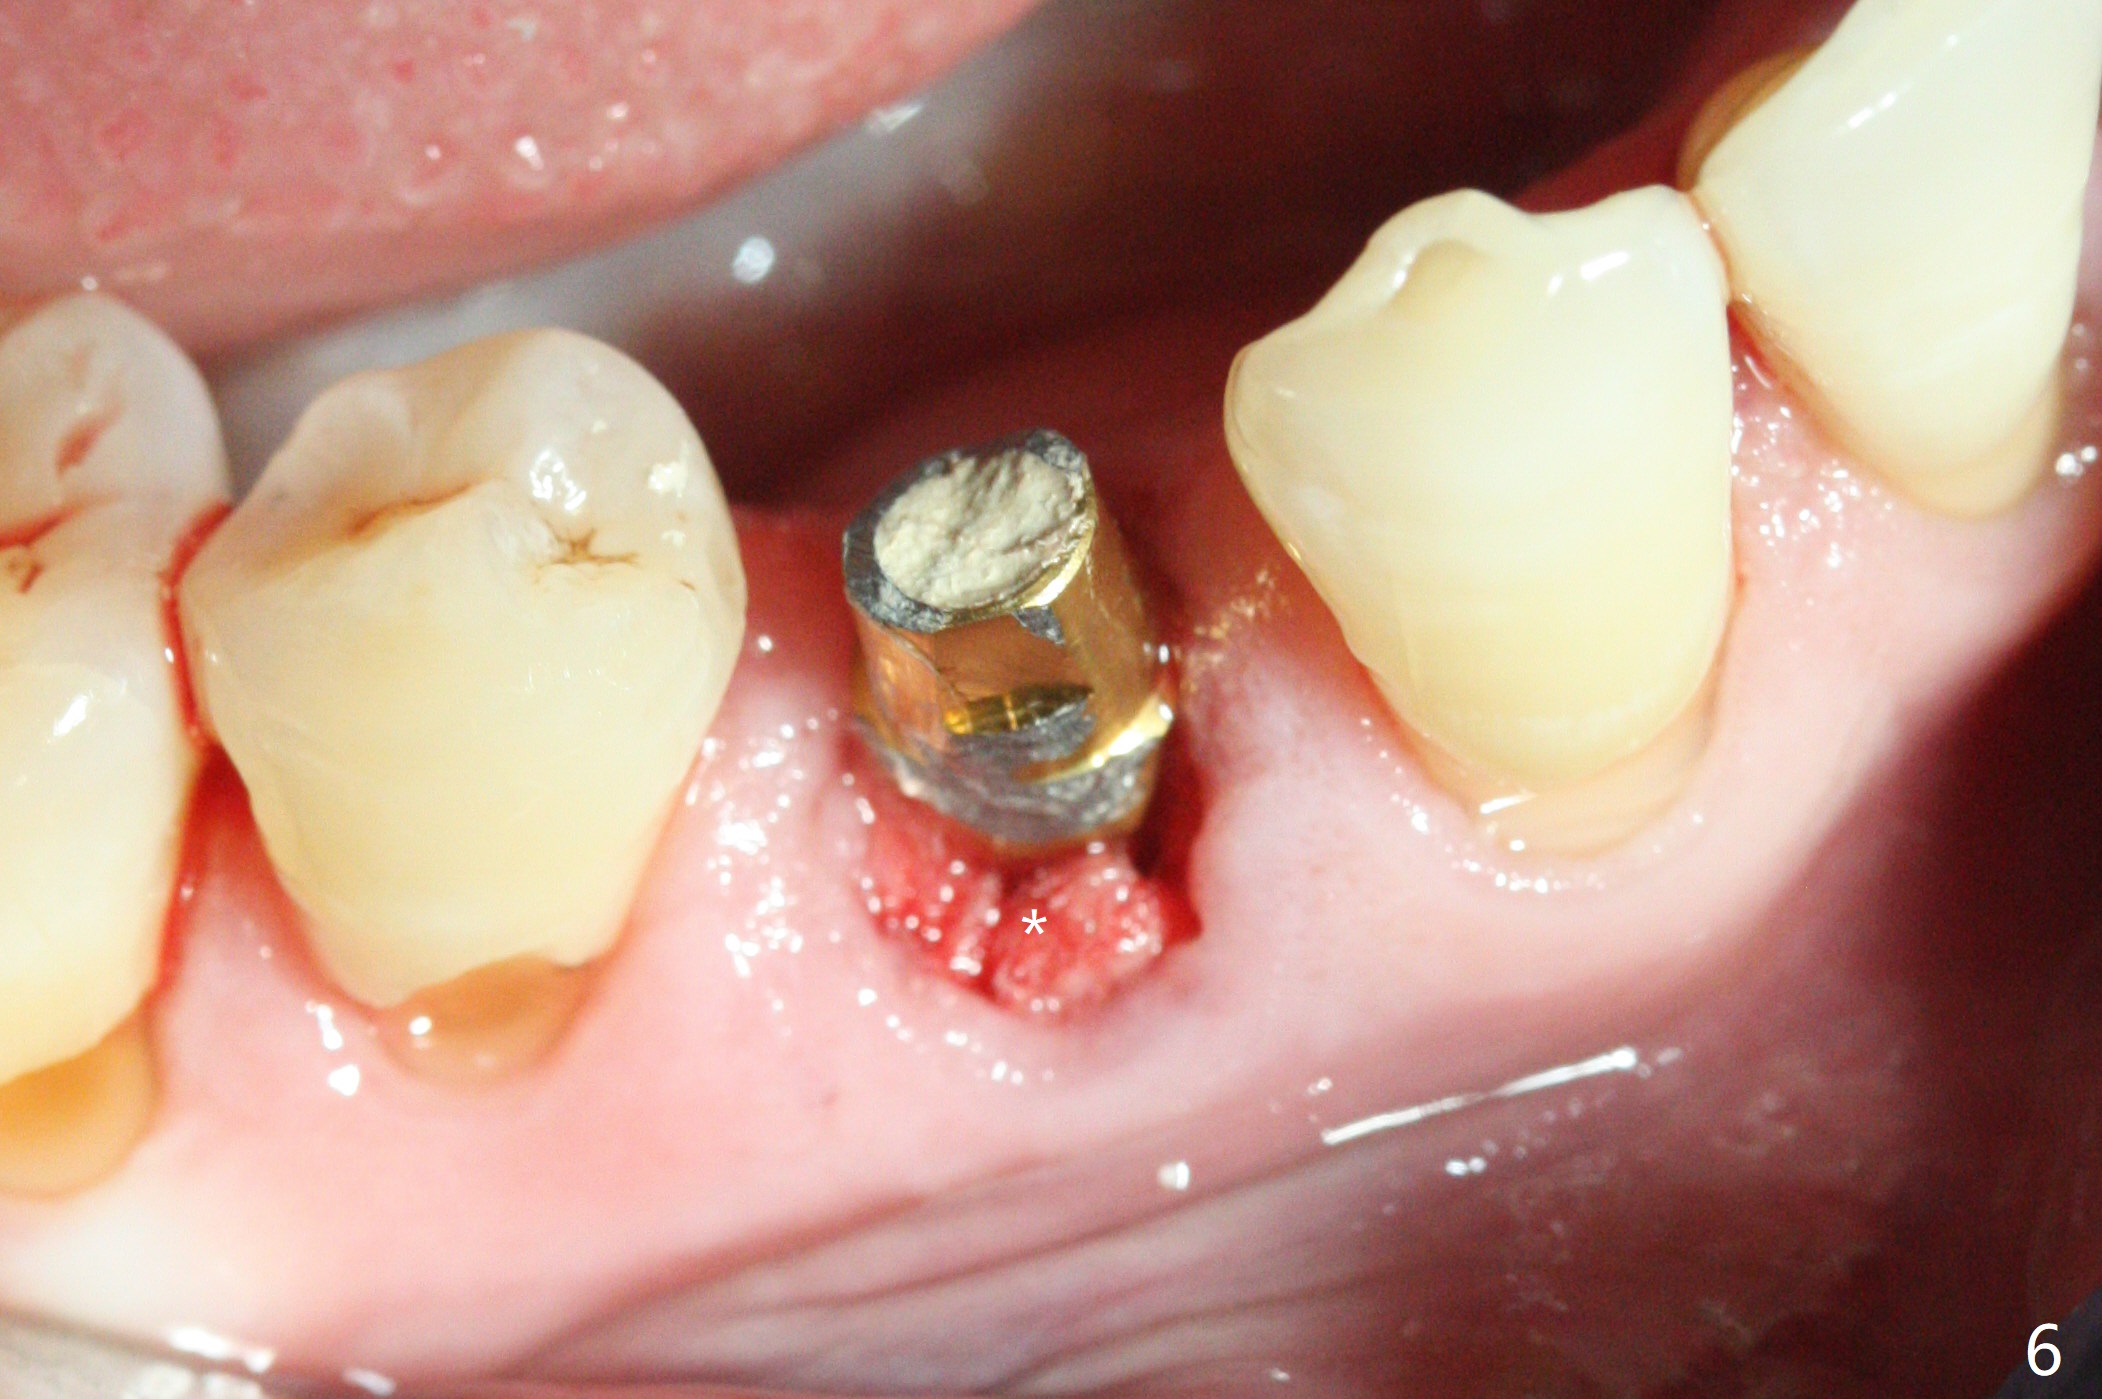

Immediately post extraction and curettage of the large buccal apical lesion, osteotomy is established in the lingual wall of the socket of #28 (slightly distal) for 17 mm vs. 15 mm socket depth (Fig.1 (red line: Mental Loop)). Following sequential osteotomy until 3.5x17 mm drill, a 4x10 mm dummy implant is partially placed with stability (Fig.2,3 (root measurement: mesiodistal 4 mm; buccolingual 7 mm)). A final implant (4x11.5 mm) is placed with insertion torque of 60 Ncm (Fig.4,5). Since the buccal crest is lower with the buccal gingival recession, the implant is intentionally placed deep as well as lingually so that autogenous bone and Vera graft mixture will be placed in the buccal gap (Fig.6 * (gauze at the moment)). The apical lesion decreases 4.5 months postop (Fig.7). Immediate implant and immediate provisional keep the papillae (Fig.8 *), but cannot prevent the buccal plate from atrophy (Fig.9 *). It appears that socket shield is able to accomplish the latter. The bone density next to the coronal threads increases 10 months post cementation (Fig.10 *) and seems to have continued to do so 1 year 4 months post cementation (Fig.11).